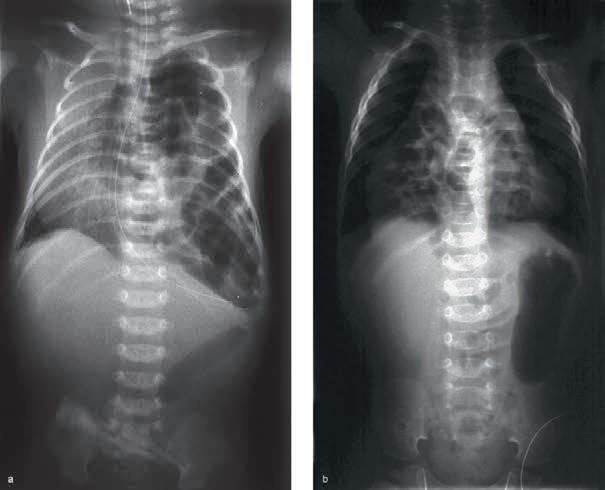

n Diagnostika

• Analýza krevních plynů: hypoxemie, vzestup pCO2

• RTG hrudníku: stadia RDS se odlišují do 4 stupňů (à tab. 1.6)

Tab. 1.6 Klasifikace RDS podle diagnostických radiologických kritérií

stupeň (stadium) radiologická kritéria

stupeň 1 jemná granulární kresba v rozsahu celé plíce

stupeň 2 současně pozitivní vzdušný bronchogram mimo srdeční stín

stupeň 3 současně neostře ohraničený srdeční stín a kontura bránice

stupeň 4 bílá plíce (à obr. 1.5)

Obr. 1.5a Syndrom dechové tísně u předčasně narozeného novorozence, RTG snímek hrudníku po intubaci, který byl provedený za 2 hodiny po porodu: mléčná snížená transparence, vzdušný bronchogram, kontury srdeční a mediastina neostré

Obr. 1.5b Syndrom dechové tísně u předčasně narozeného novorozence, RTG hrudníku, který byl provedený za 4 hodiny po podání surfaktantu, zlepšení transparence obou plicních polích při klinickém zlepšení stavu [29]

• RTG hrudníku: kardiomegalie, zvýšené prokrvení plic a edém plic (→ obr. 1.6)

Obr. 1.6 RTG hrudníku při perzistujícím ductus arteriosus s kardiomegalií a zmnoženou plicní kresbou, zejména centrálně